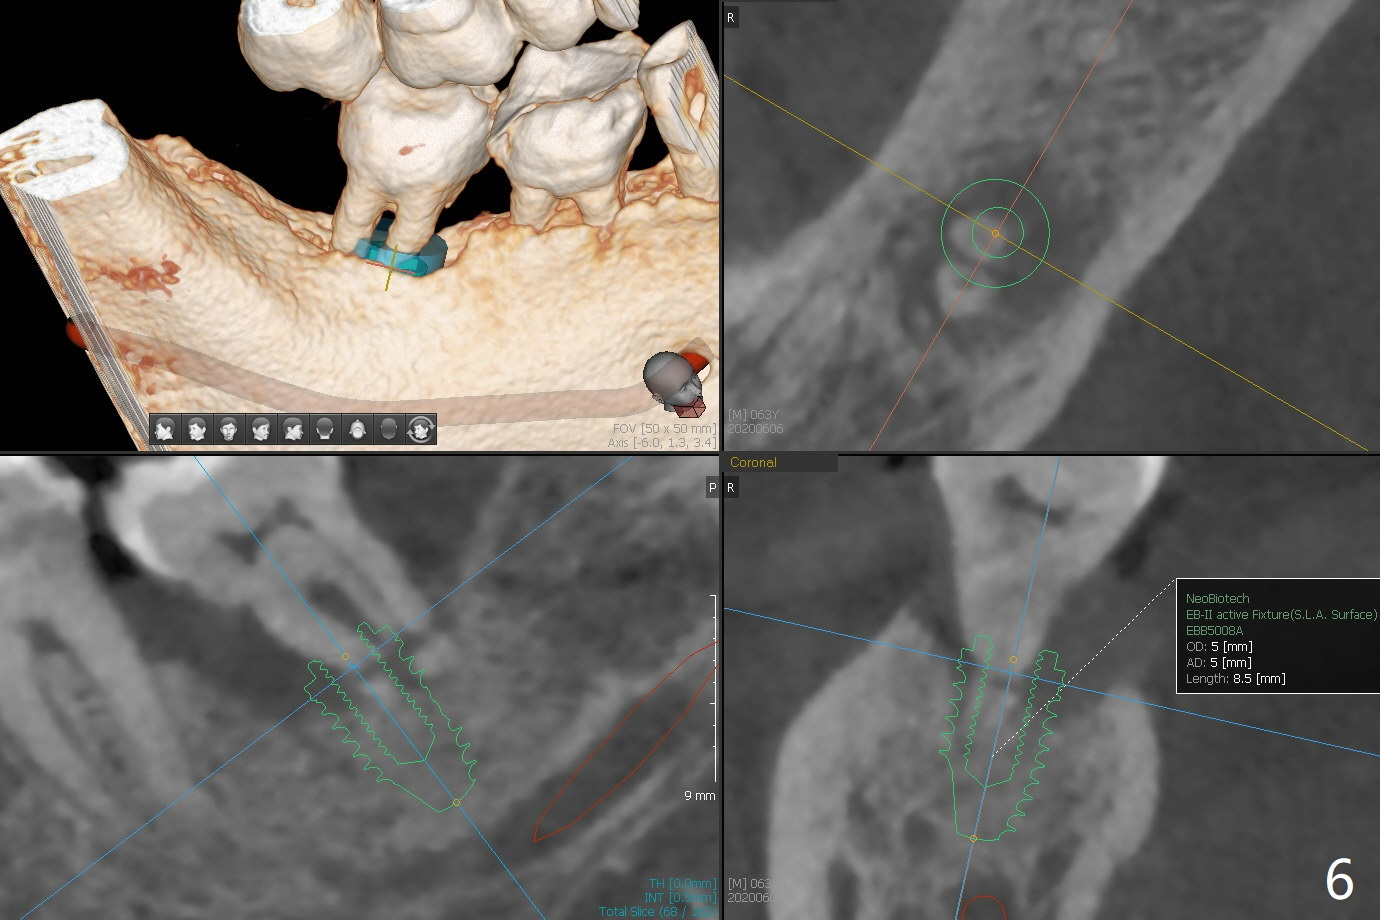

Parallel to 1st Molar

A 60-year-old man has chronic periodontitis, bruxism and malocclusion, e.g., #18 mesiolingual inclination (under occlusal trauma, Fig.1). The lingual pocket is deep with severe bone loss. After extraction, use implant positioner to gauze the size of the socket. Initiate osteotomy as mesial as possible and parallel to the 1st molar (Fig.2,3). Bone density is expected to be high. Prepare soft (1-piece) and hard (IS) tissue-level implants. The tooth remains loose 2 years later, although the patient is asymptomatic (Fig.4). Finally the tooth is symptomatic because of root tip fracture (Fig.5). Use drills with 7.3 mm stop for 4.5 or 5.0x8.5 mm implant free hand (Fig.6). The exposed implant will be covered with sticky bone (PRFx2). Prepare temporary and cemented abutments to hold bone graft in place.